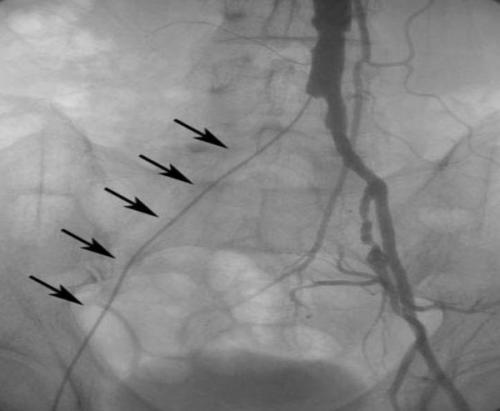

Ультразвуковое дуплексное сканирование (УЗДС) — метод диагностики первой линии. Он позволяет оценить анатомию поражения, движение крови по сосудам и морфологию, а также проверить результаты лечения. Для определения характера поражения используется измерение степени стеноза и критерии качественного и количественного анализа спектра кровотока.

КТ-ангиография необходима для уточнения анатомии поражения и планирования операции. С этой целью внутривенно вводится контрастное вещество. Изображение моделируется из серии поперечных сканирований.